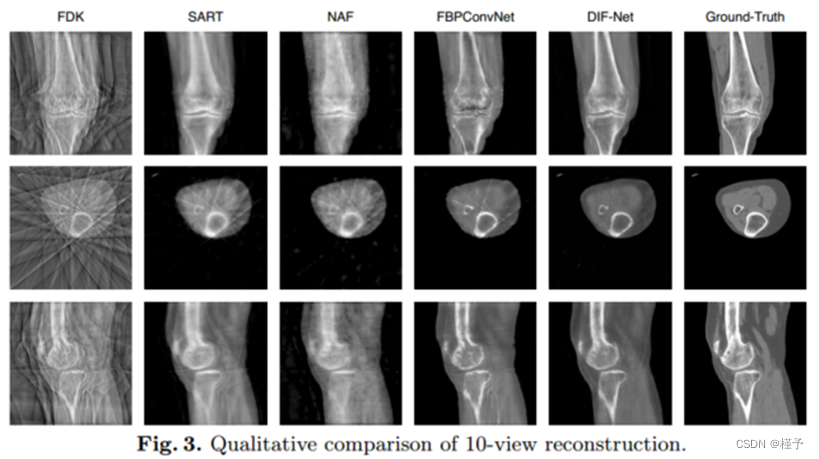

性能。如表1所示,我们在不同输出分辨率的重建设置下比较了DIF-Net与之前的四种方法[1,6,22,29](即,1283、2563)以及来自不同数量的投影视图的投影视图实验表明,我们提出的DIF-Net即使只使用6个投影视图也可以重建具有高图像质量的CBCT,其在PSNR和SSIM值方面明显优于先前的工作。更重要的是,DIF-Net可以直接应用于重建具有不同输出分辨率的CT图像,而不需要模型重新训练或修改。如图3所示的视觉结果,FDK [6]由于缺乏足够的投影视图而产生具有许多条纹伪影的结果; SART [1]和NAF [29]产生具有良好形状轮廓的结果,但缺乏详细的内部信息; FBPConvNet [11]重建了良好的形状和中等的细节,但仍然存在一些条纹伪影;我们提出的DIF-Net可以重建出高质量的CT图像,具有更好的形状轮廓、更清晰的内部信息和更少的伪影。2补充资料中给出了输入视图数量的更直观的比较。